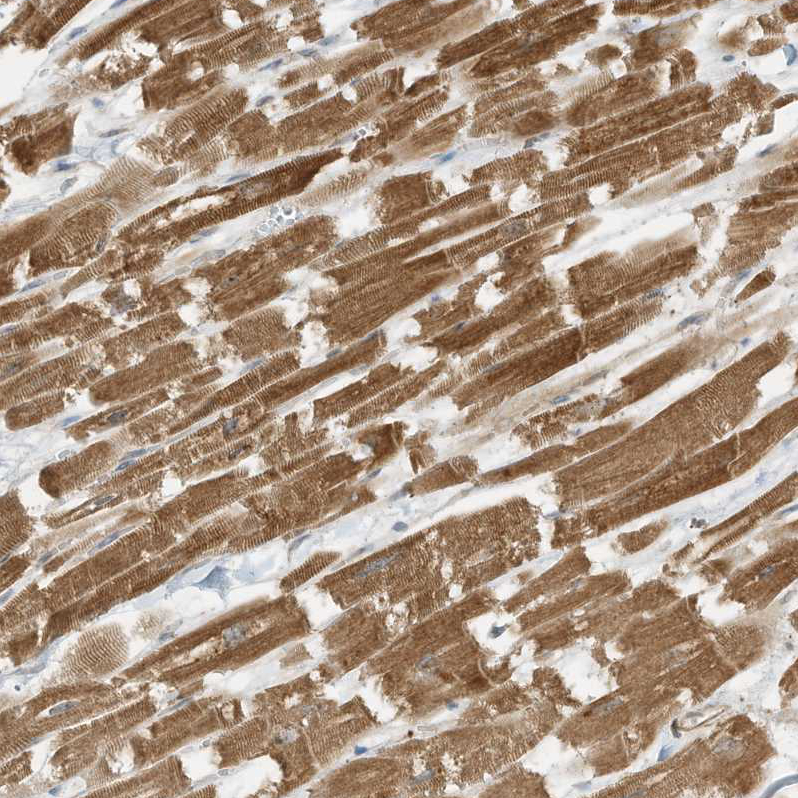

Immunohistochemical staining of human heart muscle shows strong cytoplasmic positivity in cardiomyocytes.